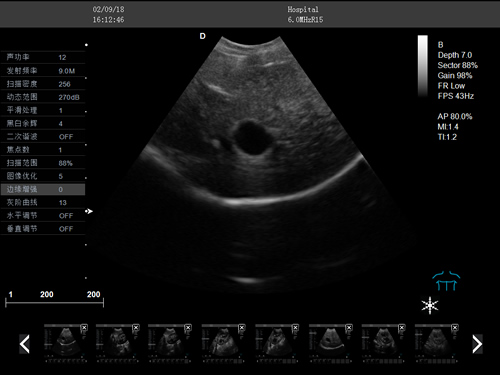

F3-VET推車式獸用彩超機

動物寵物超聲診斷儀

彩色多普勒動物超聲診斷儀

·中小動物的肝、膽,脾、腎、膀胱、子宮、妊娠等各組織器官的檢查和病變的診斷